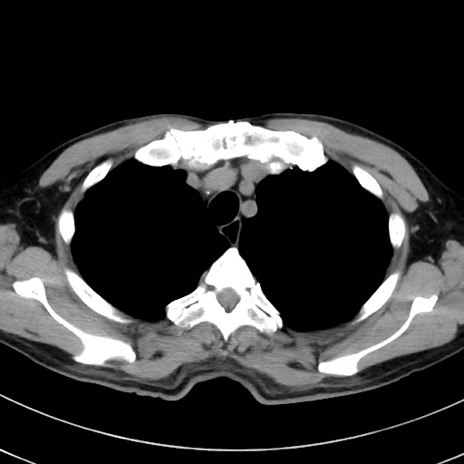

症例38(横断像)

【症例】70歳代 男性

【主訴】腹痛・嘔吐

【現病歴】昨晩より、嘔吐・腹痛あり。今朝になっても嘔吐あり。来院。

【既往歴】心臓バイパス手術、開腹胆摘、腸閉塞

【身体所見】BP 107/71mmHg、HR 116/min、腹部:平坦、軟、下腹部に軽度圧痛あり。反跳痛なし。

【データ】WBC 15100、CRP 0.32